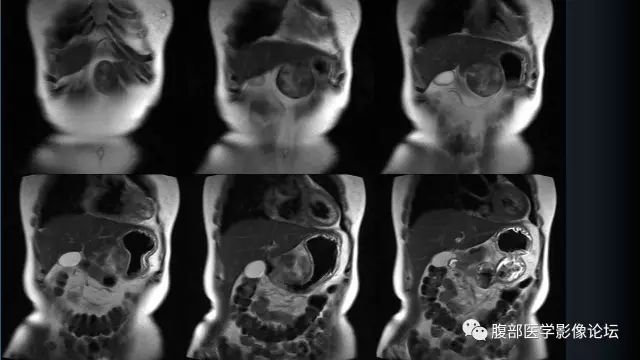

影像表现

形态规则,边缘清晰,多为梭形或类圆形。 CT密度均匀,与肌肉类似,出血坏死钙化少见。增强动脉期呈轻度不均匀强化,延迟强化进一步强化,趋于均匀。MRT1WI多呈等或略高信号,T2WI信号多样,可为高/略高/低信号,大多为不均匀高信号。